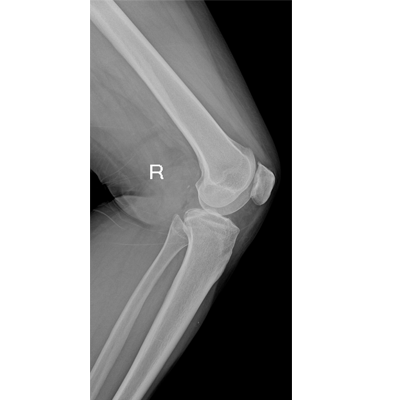

輕量化設(shè)計(jì) 小巧靈活 PLX5100

用于影像科、急診室、病房、ICU、手術(shù)室等多場(chǎng)景應(yīng)用。

● 組合式X射線發(fā)生器

● 采用閉環(huán)控制技術(shù),準(zhǔn)確控制射線劑量

● 數(shù)字化無線平板成像,操作簡(jiǎn)便,成像質(zhì)量高